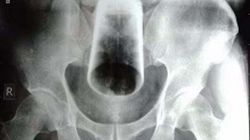

Witam, ma naprawdę niepokojacy problem kolega dla zartu włożył mi ciało obce do odbytu. Próbowałem je usunąć naturalnie lecz bezskutecznie. Kał na szczęście wyszedł bez większego problemu dlatego przynajmniej nie ma zaparacia lecz ciało obce nadal tam zostało. Co mam robić czy jak udam sie na SOR to czy będę musiał kogoś o tym powiadomić? Ponieważ jest to dla mnie bardzo wstydliwe.

Jeżeli zgłosi się Pan do szpitala bądź poradni to z całą pewnością będzie Pan musiał uzasadnić powód swojej obecności. Wymaga Pan konsultacji chirurgicznej.